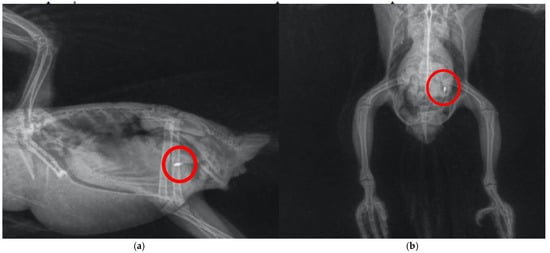

Specimens of Aratinga jandaya voluntarily surrendered and treated at the Wildlife Sector of the Veterinary Hospital (HVSAS) at the Federal University of Pará (UFPA), in Castanhal/PA, exhibited symptoms (regurgitation, apathy, and disoriented behavior) of heavy metal poisoning, possibly Hg and/or Zn, and the presence of a radiopaque foreign body in the celomic cavity radiographic exam suggestive of portions of the gastrointestinal tract (Figure 1). After symptomatic generalist treatment (Ca-EDTA 70 mg/kg PO, BID for 7 days, fluid therapy with lactated Ringer’s, vitamin supplementation with complex B and omega-3, and nebulization), the animals improved, indicating the possibility of intoxication and raising awareness of the potential contact of these individuals with metals in peri-urban and urban areas where the presence of this and other psittacids species is growing (Figure 2). Although radiographic findings and clinical signs strongly supported metal ingestion, the exact nature of the metallic material was not confirmed via residue analysis. Therefore, differential diagnoses such as mycotoxicosis, organophosphate exposure, or chronic intoxication by environmental zinc particularly in urban-adapted psittacids cannot be ruled out and may present with overlapping symptoms that also respond to chelation and supportive therapies [10,21,30].

A similar case was described by Pinheiro et al [29] in Nymphicus hollandicus, which also culminated in clinical improvement due to prompt symptomatic treatment, demonstrating that even psittacids known to be domestic and/or in direct contact with humans are more susceptible to heavy metal exposure. Santos et al [31] also detected the presence of radiopaque content (Figure 3) and incoordination in free-living Brotogeris chiriri that responded well to treatment against heavy metal intoxication, restoring full function to the animals. It is important to note the scarcity of reports with descriptive diagnoses regarding the type of metal found, which is a focal point of importance to be better determined in the care of these individuals despite the difficulties in collection and testing, aiming for more accurate treatment directed at the underlying cause. Cases in companion or urban-adapted psittacids, such as Nymphicus hollandicus [29] and Brotogeris chiriri [31], illustrate that even species living in close proximity to humans are not exempt from environmental exposure to heavy metals. On the contrary, these birds may be at elevated risk due to contact with anthropogenic materials in domestic or peri-urban environments. Moreover, because they are under closer human observation, intoxication symptoms are more likely to be recognized and reported compared to free-ranging individuals.

Figure 3. Radiography of the celomic cavity performed in Brotogeris chiriri. (a) Right lateral–lateral position demonstrating the particle with high radiopacity; (b) ventro-dorsal position demonstrating the particle with high radiopacity. Adapted from Santos et al. [31].